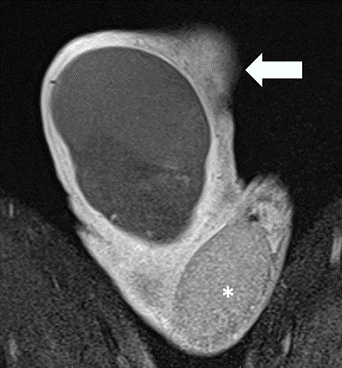

La RM evidenció TD aumentado de tamaño, horizontalizado y ascendido, con señal hiperintensa en secuencias T1 y T2, sin captación de contraste (Figura 1a, 1b).

TD ascendido, horizontalizado, con moderado aumento de tamaño y señal heterogénea predominantemente hipointensa (flecha) comparar con testículo contralateral de características conservadas (*). Origen: Servicio de Diagnóstico por Imágenes. Hospital Italiano de Buenos Aires. Buenos Aires, Argentina. 2021.

Figura 1a Imagen coronal secuencia T2

TD con pérdida de su morfología ovoidea presenta ausencia completa de captación de contraste en todo el parénquima (Flecha) compararse con TI que muestra captación normal (*). Origen: Servicio de Diagnóstico por Imágenes. Hospital Italiano de Buenos Aires. Buenos Aires, Argentina. 2021.

Figura 1b Imagen coronal secuencia T1